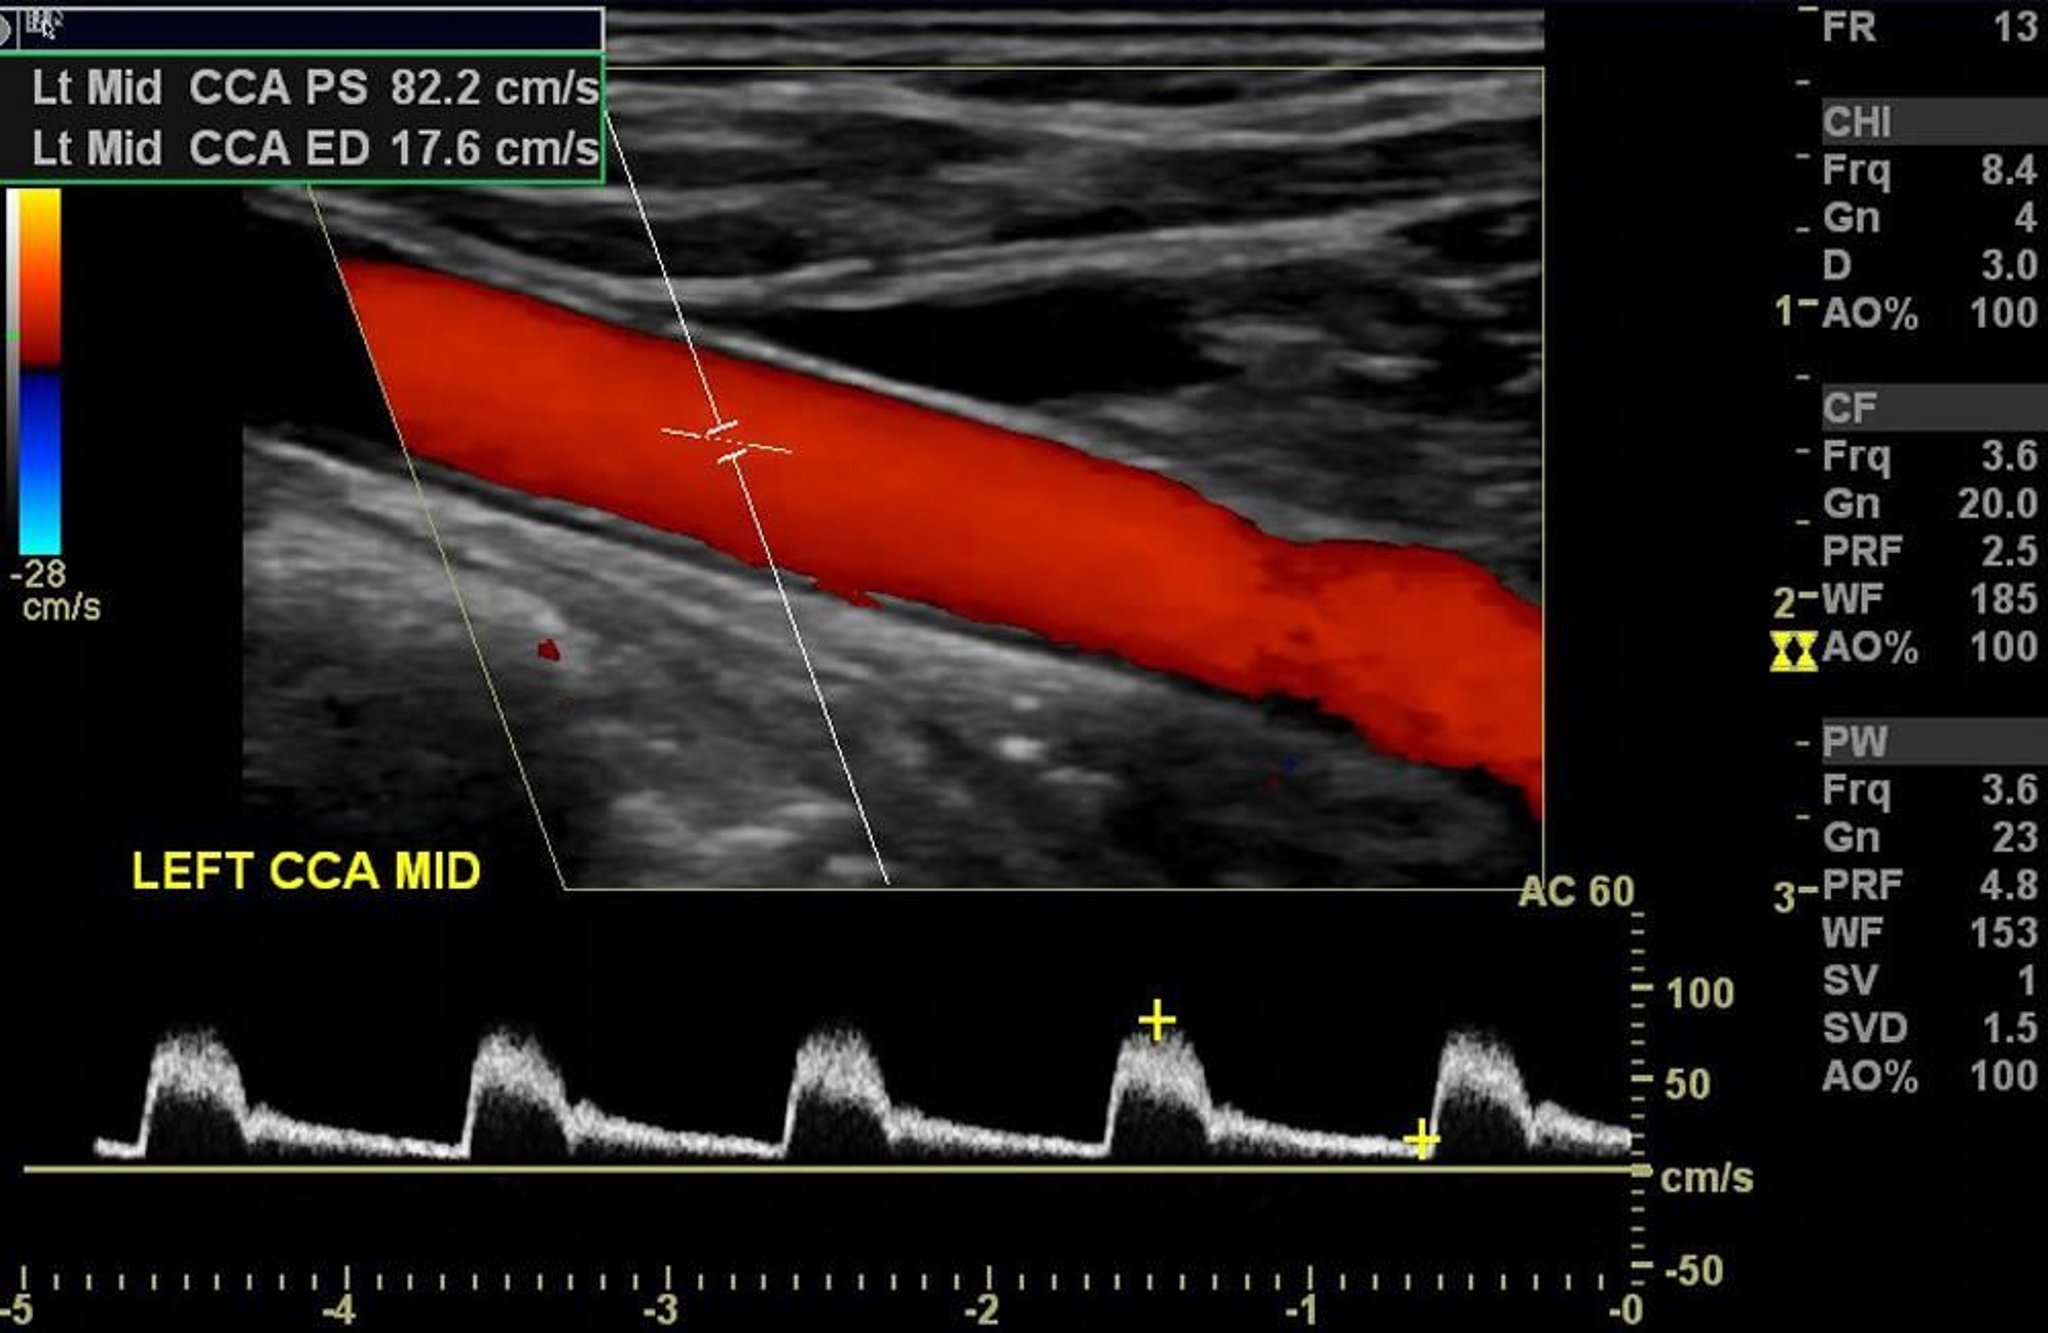

この左頸動脈のカラードプラ超音波検査では,有意な狭窄のない正常な動脈血流がみられる。

Image courtesy of Hakan Ilaslan, MD.

カラードプラ超音波検査では,ドプラ法による血流の情報が,血流を色で示したカラー画像に変換される;グレースケールの解剖学的な超音波画像上に表示される。血流の方向は色合いで示される(例,トランスデューサーに向かう血流は赤,トランスデューサーから遠ざかる血流は青)。平均血流速度は色の明るさにより示される(例,明るい赤はトランスデューサーに向かう速い血流を示す;暗い青はトランスデューサーから遠ざかる遅い血流を示す)。